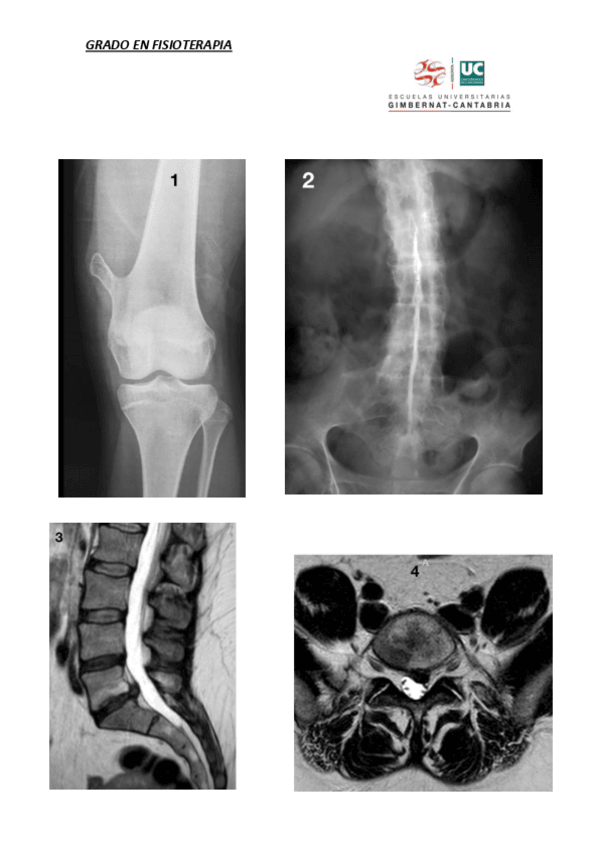

REUMA

He publicado nuevos apuntes de 2º Patología Humana II: REUMA

5.-artropatia-degenerativa-perif.pdf

7.-PartesBlandas-generalidades.pdf

11.-Partes-blandas-Rodilla.pdf

9.-Partes-blandas-codo-muneca-y-mano.pdf

29.-Enfermedades-inflamatorias.pdf

3.-Artrosis-generalidades.pdf

He publicado nuevos otros de 2º Patología Humana II: Reuma

EXAMEN-PATO-RAYOS-2018-2019.pdf

EXAMENES-REUMA-TODOS.pdf

ImagenesExamen-PatoII201819-1.pdf

PATOLOGIA-II-REUMATOLOGIA.pdf

Preguntas-hakoot.pdf

radiologia.pdf